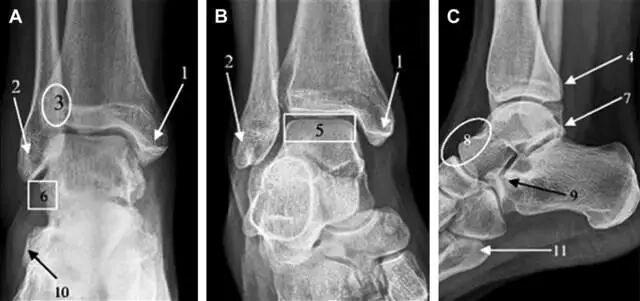

急诊科医生常遇到的一个问题是:踝关节疼痛。对于这类患者,想要分辨是否存在骨折,X 线检查是主要手段。然而,由于各种原因,有些踝部骨折非常容易漏诊。

首先,来看踝关节骨折的高危区(图 1)。

图 1 踝部探查模板。阅片时,需对踝关节的前后位片(A)、内旋转位片(B)侧位片(C)仔细阅读,逐一详细排查。上图中的骨折:1. 内踝骨折,2. 外踝骨折,3. 胫骨结节骨折,4. 胫骨后踝骨折,5. 距骨骨软骨骨折,6. 距骨外侧突骨折,7. 距骨后突骨折,8. 距骨舟骨关节背侧骨折,9. 跟骨前突骨折,10. 跟骨骨折嵌插入趾短伸肌,11. 第五跖骨底骨折

16胫骨后踝骨折

涉及到三角韧带和外侧副韧带(LCL)的复杂性骨折常常不难发现,尤其是存在表面软组织肿胀时。然而,后胫腓韧带牵拉引起的胫骨后踝骨折则很难发现。这些骨折大小不一(图 2),却很重要,因为他们常与胫骨远端螺旋骨折有关,或者是三踝骨折的一部分。

图 2 胫骨后踝骨折。A 侧位片示来源于胫骨后踝的一个小骨折碎片(箭头),因踝部扭伤导致B 另一位跖屈损伤的患者,侧位片示一个大骨折块(箭头)